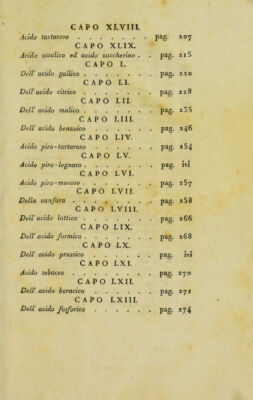

Copy 1, Volume 2

Istituzioni di chimica-farmaceutica ... / del prof. Antonio Porati ; Le quali formano il soggetto delle lezioni che fa nella scuola del Liceo dipartimentale d'Olona, stabilita nell'Ospitale Civile di Milano.

- Porati, Antonio

- 1804